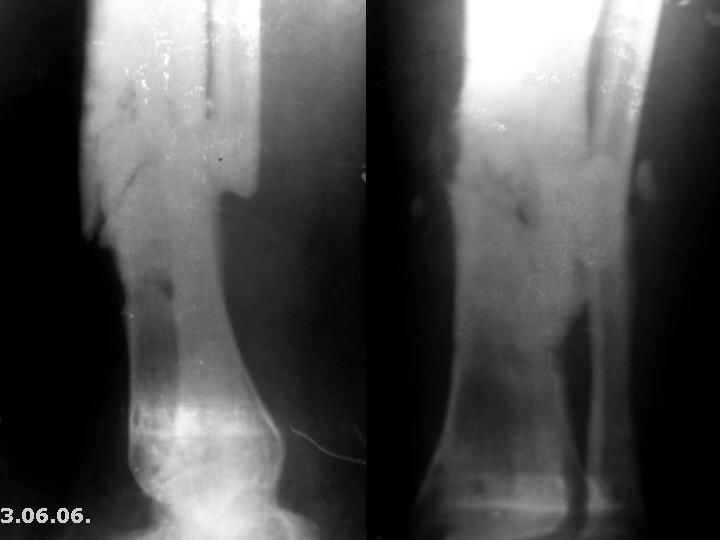

Мужчина, 29 лет. Состоит на лечении в ЦРБ.Диагноз: Замедленно сростающийся со смещением повторный перелом обеих костей левой голени вс/3-н/3, состояние после ВЧКО, хронический остеомиелит костей левой голени, свищевая форма,трофический синдром, смешанная контрактура левого коленного, голеностопного суставов.

Травма 20.12.04. - открытый 2Б тип, оскольчатый перелом обеих костей левой голени в с/3-н/3 сосмещением отломков (ДТП). 20.12.04.- ВЧКО костей голени АВФ спице-стержневого типа, ПХО ран.Лечился амбулаторно. Перелом длительно не сростался. АВФ демонтирован 22.06.05., разрешена нагрузка на ногу, после чего появилась подвижность в области перелома. 8.07.05. - ВЧКО, туннелизация по Беку. Течение осложнилось развитием спицевого остеомиелита, 1.11.05. АВФ демонтирован, получал консервативное лечение. После нормализации состояния 17.11.05.- секвестрэктомия, ВЧКО голени.12.04.06. АВФ демонтирован.

3.06.06.повторная травма - закрытый повторный перелом левой б/б кости в с/-н/3, лечился методомгипсовой иммобилизации.

Место болезни - ось голени искривлена. Kеллоидные рубцы в местах проведения спиц, по передней поверхности голени. По передней и внутренне-боковой поверхности голени в определяется 3 свища с умеренным серозным отделяемым. Отек голени и сустава, движения в коленном и голеностопном суставах ограничены, неврологических расстройств в стопе нет.

Снимки, конечно, оставляют желать. Ладно, пробуем предложить решение в условиях недостатка информации. В том числе не зная о доступных на месте методах лечения.

Если первое - снова остеосинтез аппаратом, остеотомия малоберцовой кости, дозированное исправление оси и длины.

Если инфицированный ложный сустав - лучше перевести пациента в более оснащенное чреждение.